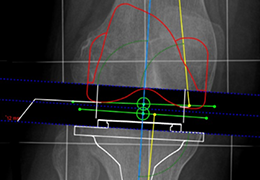

Segmentation

Segmentation of tissue (e.g., isolating the brain, differentiating gray and white matter) is performed using region-growing methods, filter operations as well as the application of 3D templates. Using the mouse it is very easy to explore a 3D volume with superimposed pseudocolor-coded statistical maps in a four-window representation showing a sagittal, coronal, transversal and oblique section. Based on a (segmented) 3D data set a three-dimensional reconstruction of the subjects' head and brain can be calculated and displayed from any specified viewpoint using volume or surface rendering.

Advanced segmentation tool means even higher quality segmentation of grey and white matter and boundaries.